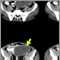

Intra-abdominal abscess, CT scan

A CT scan of the abdomen will usually reveal an intra-abdominal abscess. After the CT scan is done, a needle may be placed through the skin into the abscess cavity to confirm the diagnosis and treat the abscess.